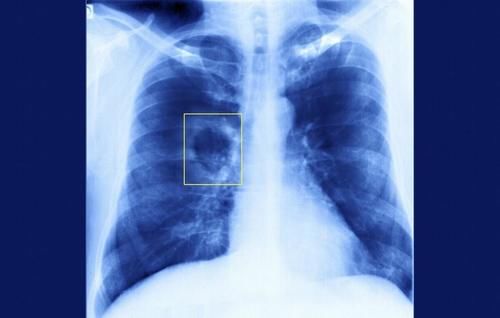

世界防治结核病日|预防肺结核可以这么做

??今天是世界防治结核病日,这提醒了我们,在现在这样的环境下,还存在着一种古老而顽固的疾病。

结核病属于慢性传染病,它有个大家很熟悉的俗称,叫“肺痨”,是由结核杆菌引起的,主要会侵害人体的肺部,也就是肺结核。

肺结核是呼吸道传染病,所以人人都有被感染的可能。